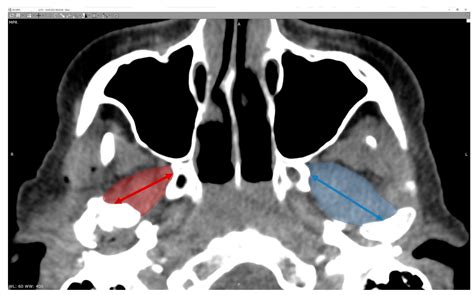

Radiological Identification

In modern medicine, identifying the medial pterygoid plate through imaging—such as Computed Tomography (CT) or Cone Beam CT (CBCT)—is essential for diagnosing anatomical variations or pathologies. Because the bone is relatively thin, high-resolution imaging is required to visualize it clearly, especially when assessing for fractures or developmental anomalies of the skull base.

• Symmetry: Assessing both plates for symmetry can help identify potential developmental issues like hemifacial microsomia.

• Fracture Patterns: In cases of blunt trauma to the face, the pterygoid plates are often involved, and their displacement can indicate the severity of midface fractures (Le Fort classification).

• Neoplastic Involvement: Tumors arising from the nasopharynx often involve the medial pterygoid plate, leading to bone erosion that is highly visible on imaging studies.

💡 Note: Use multiplanar reconstruction (MPR) in CBCT software to accurately view the coronal and axial cross-sections of the pterygoid process for better diagnostic precision.